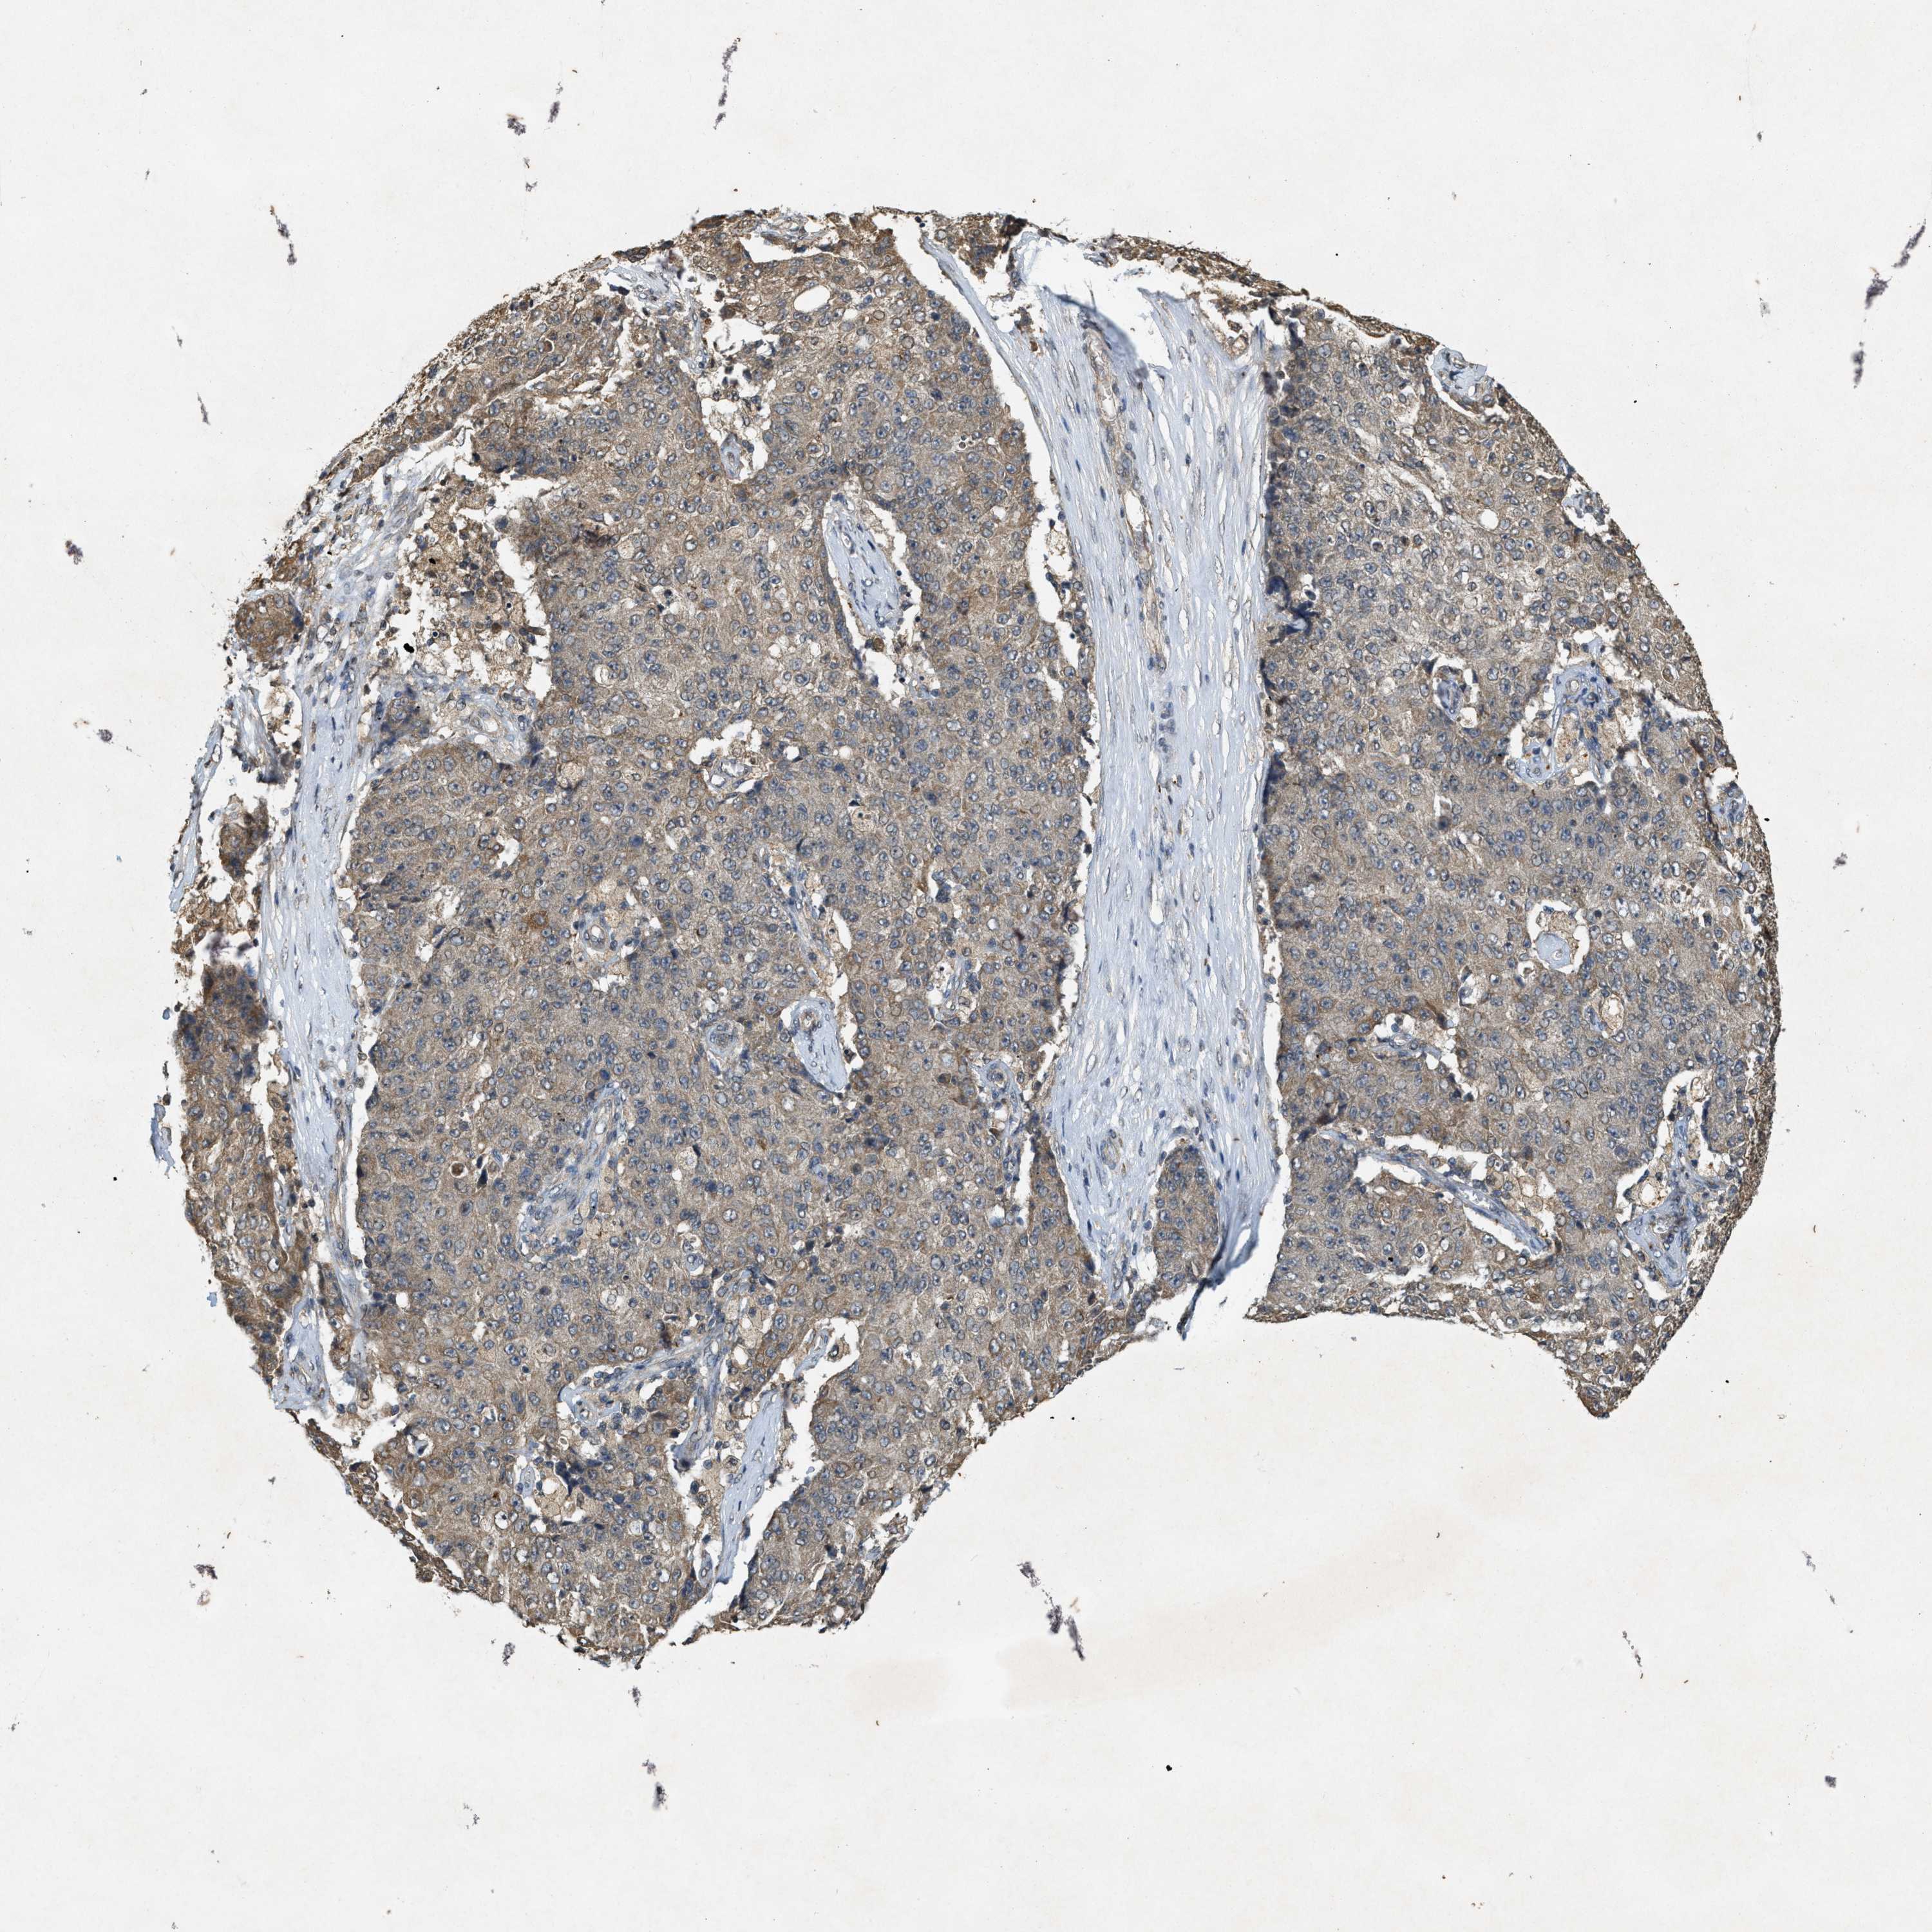

OVARIAN CANCER - Protein expressioni

A mouse-over function shows sample information and annotation data. Click on an image to view it in a full screen mode. Samples can be filtered based on level of antibody staining by selecting one or several of the following categories: high, medium, low and not detected. The assay and annotation is described here.

Note that samples used for immunohistochemistry by the Human Protein Atlas do not correspond to samples in the TCGA dataset.

Antibody stainingi

Antibody staining in the annotated cell types in the current human tissue is reported as not detected, low, medium, or high, based on conventional immunohistochemistry profiling in selected tissues. This score is based on the combination of the staining intensity and fraction of stained cells.

Each image is clickable and will lead to virtual microscopy that enables deeper exploration of all samples and also displays staining intensity scores, fraction scores and subcellular localization as well as patient and tissue information for each sample.

Antibody HPA058432

Antibody CAB022079

Cystadenocarcinoma, serous, NOS